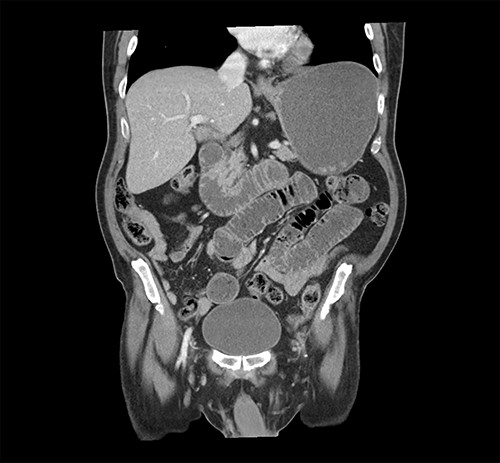

At the time of his PET scan, the patient acutely developed diffuse abdominal pain and vomiting. The scan was aborted and the patient was rushed to the emergency department. An abdominal X-ray and a CT scan of the abdomen and pelvis showed small bowel dilatation, but there was no intestinal mass lesion (Fig. 1). He was placed on nasogastric tube decompression. The patient reported having melena that morning. The hemoglobin was found to be 6.1 g/dl and a tagged RBC nuclear scan showed active gastrointestinal bleeding (Fig. 2) at the approximate location of the transition zone of the small bowel obstruction seen on CT.

CT of the abdomen and pelvis showing evidence of small bowel obstruction with dilated stomach and loops of the small intestine.

Radionuclide RBC scan showing active hemorrhage within the mid-small intestine (arrow).